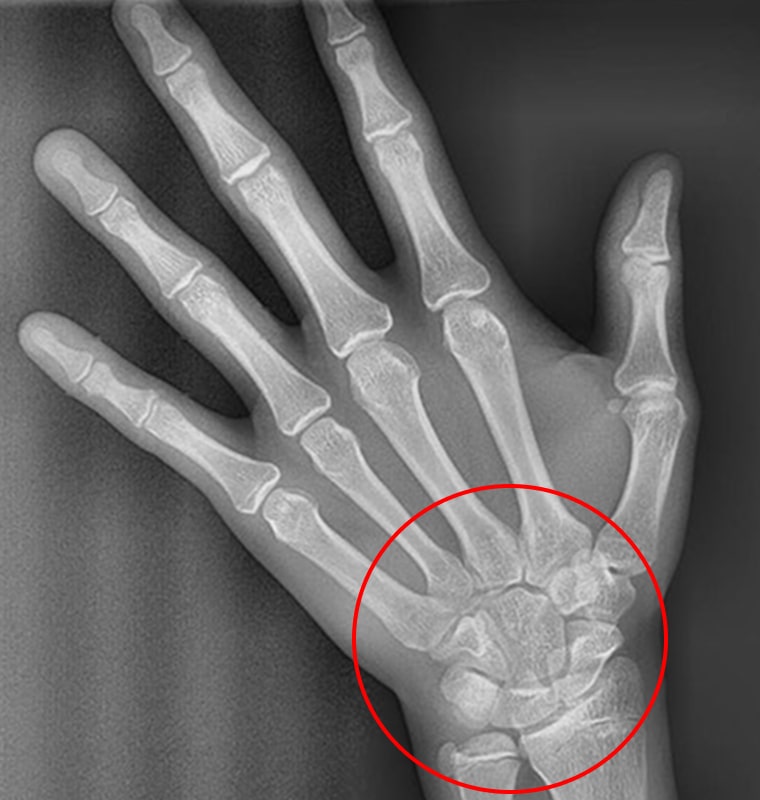

STEP 03 손목뼈 미융합 + 가운데 손가락 마디뼈 융합

손목뼈가 미융합 상태이면서 손가락 마디뼈가

융합된 상태는 성장기 후반부를 나타냅니다.

이 시기는 골격 교정보다는 치아 배열과 교합 정리에

중점을 둔 치료가 주로 이루어지며, 남아 있는 소량의

성장 여력을 최대한 활용하는 것이 중요합니다.